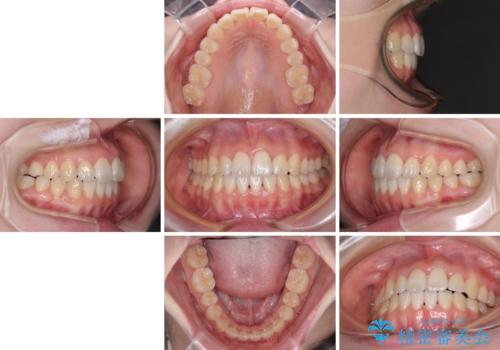

- 前歯の捻れと、ちょっとした出っ張りを気にして来院された患者様です。

歯と歯の間を削る(IPR)ことでデコボコを解消し、インビザラインで整えることとしました。

インビザライン治療特有の奥歯が接触しない時期が続き、当初予定よりも期間がかかりましたが、最終的には安定した咬み合わせと、整った前歯になりました。